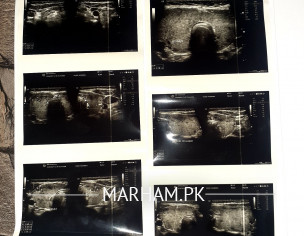

Asking For Sister, Female 35, Islamabad

Attachments Please guide

multinodular goiter

need total thyroidectomy

kindly check mam I posted the report pic

kindly chk

You need Total thyroidectomy Surgery!

there is no other option.